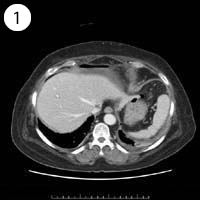

57歳 女性

単純CT

造影CT